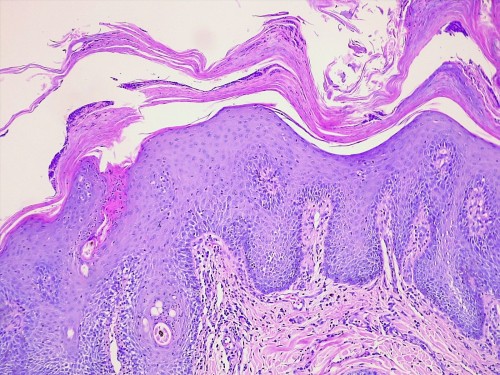

Lors de la consultation de contrôle, les lésions sont toujours présentes mais les examens cliniques et microscopique montrent une nette amélioration des surinfections. Des biopsies sont réalisées. L’analyse histopathologique montre une dermatite hyperplasique spongiotique périvasculaire caractérisée par une parakératose épidermique et folliculaire diffuse accompagnée d’une hypogranulose et compliquée de lésions de pyodermite superficielle. L’aspect histologique conforte la suspicion clinique de dermatose répondant à l’administration de Zinc de type 1. (cf. photos 5)